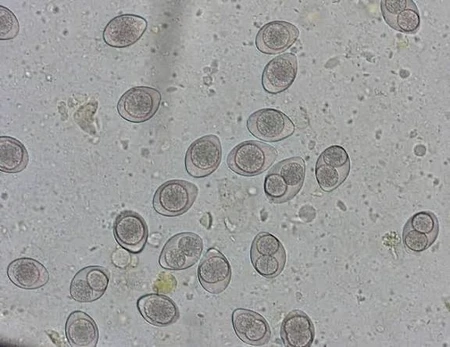

Les protozoaires et cestodes

Nommez les protozoaires et les cestodes illustrés.

Protozoaire

Cestode